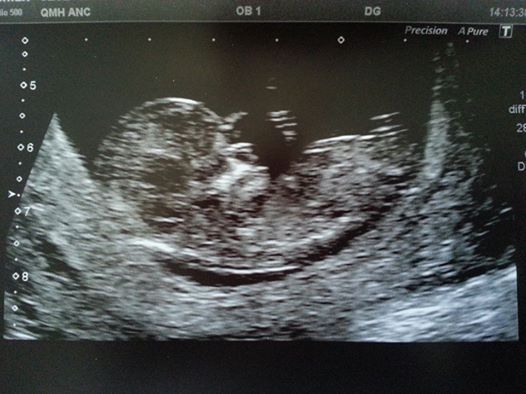

Hello.. had my scan yesterday, all went well Smile. Me and DH just sat in dumbfounded silence!!! I was expecting tears, but I think my moods have calmed down a bit.. Got several pics (free) to take away..

Great news in the scan and a fab picture miffy it is just so amazing isn't it. A little thing inside you!!

Sorry, less of a 'thing' and more of a 'baby'!!!

Thanks foscar yeah I wasn't convinced there was anything there until we could actually see it! Confused